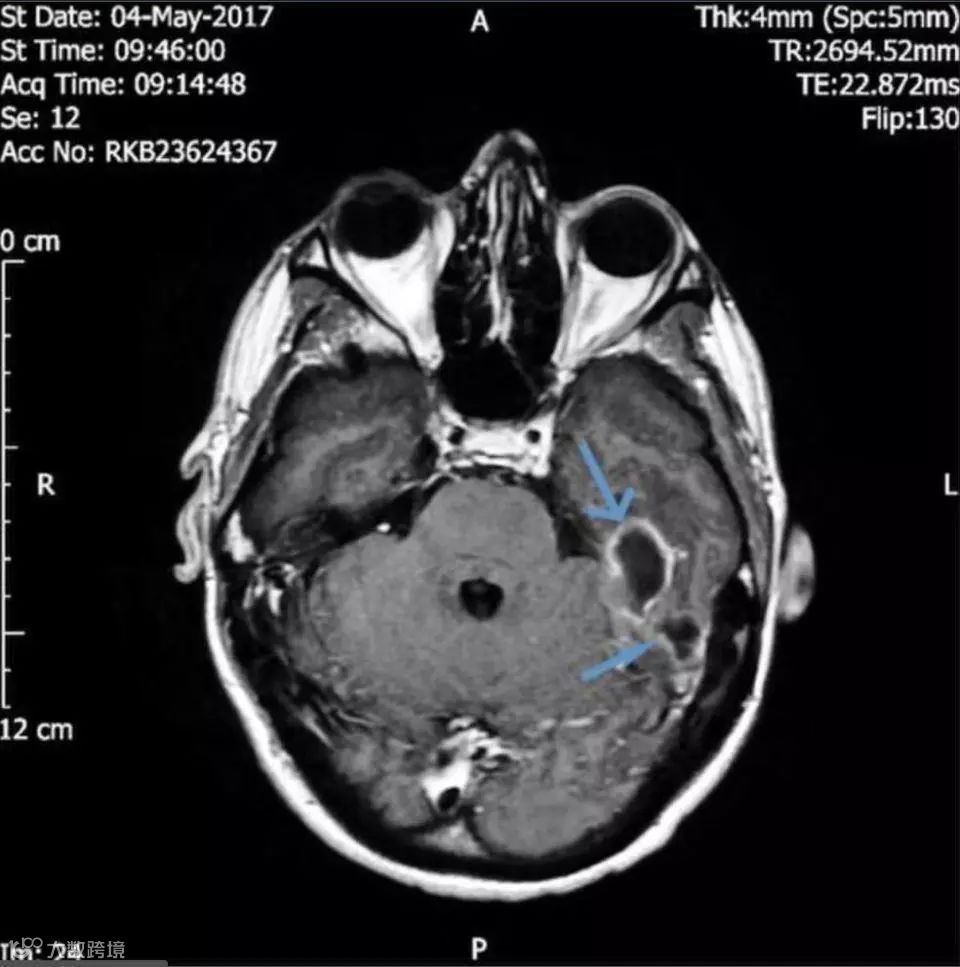

医学团队的CT扫描显示:他的头骨下靠近左耳道的位置有两块充满脓液的肿块,

再晚治疗情况就危险了。

终于在脑成像的帮助下他们发现男子的

耳道中有一个异物。

经过鉴定,导致严重感染的东西是

一小撮棉花。